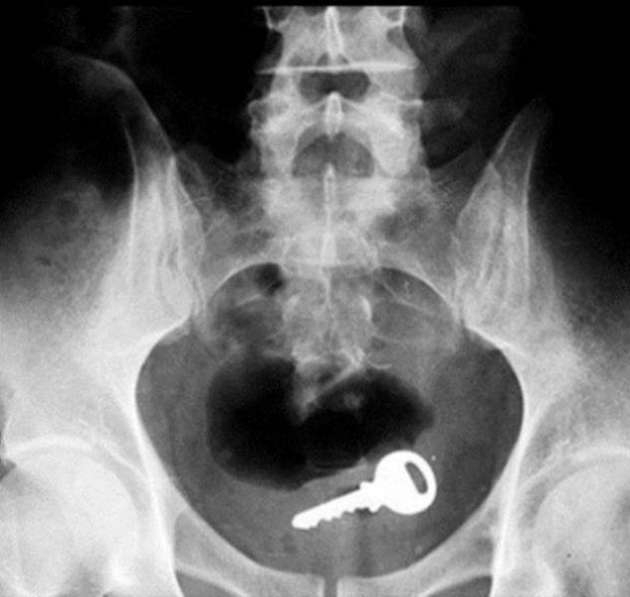

İÇİNDEKİ ŞEYE RÖNTGEN UZMANLARI ŞOK OLDU!

RÖNTGEN UZMANLARI ŞOK OLDU!

,Dünyada çekilen bu röntgenler hem röntgen uzmanlarını hemde görenleri şok ediyor...